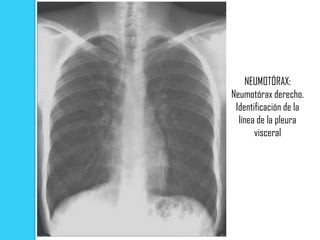

NEUMOTÓRAX:

Neumotórax derecho.

Identificación de la

línea de la pleura

visceral

NEUMOTÓRAX: Neumotórax derecho. Identificaciónde la línea de la pleura visceral